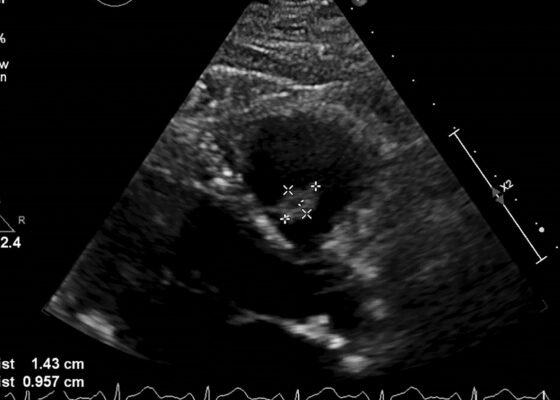

DOI: https://doi.org/10.21980/J8206GA point-of-care ultrasound of the urinary tract was performed, evaluating the kidneys and bladder. When imaging her kidneys, right-sided hydronephrosis was noted with a normal appearance to the left kidney. To further evaluate, a curvilinear probe was placed on her bladder with color doppler to assess for ureteral jets. Ureteral jets are seen as a flurry of color ejecting from each of the ureters as urine is released from the ureterovesical junction. In a healthy patient, this finding should be seen ejecting from both ureters every 1-3 minutes as the kidneys continue to filter the blood and create urine to be stored in the bladder. In our patient, however, ureteral jets were only noted on the left side (arrow), which was significant in further verifying our suspicion of right ureteral obstruction.